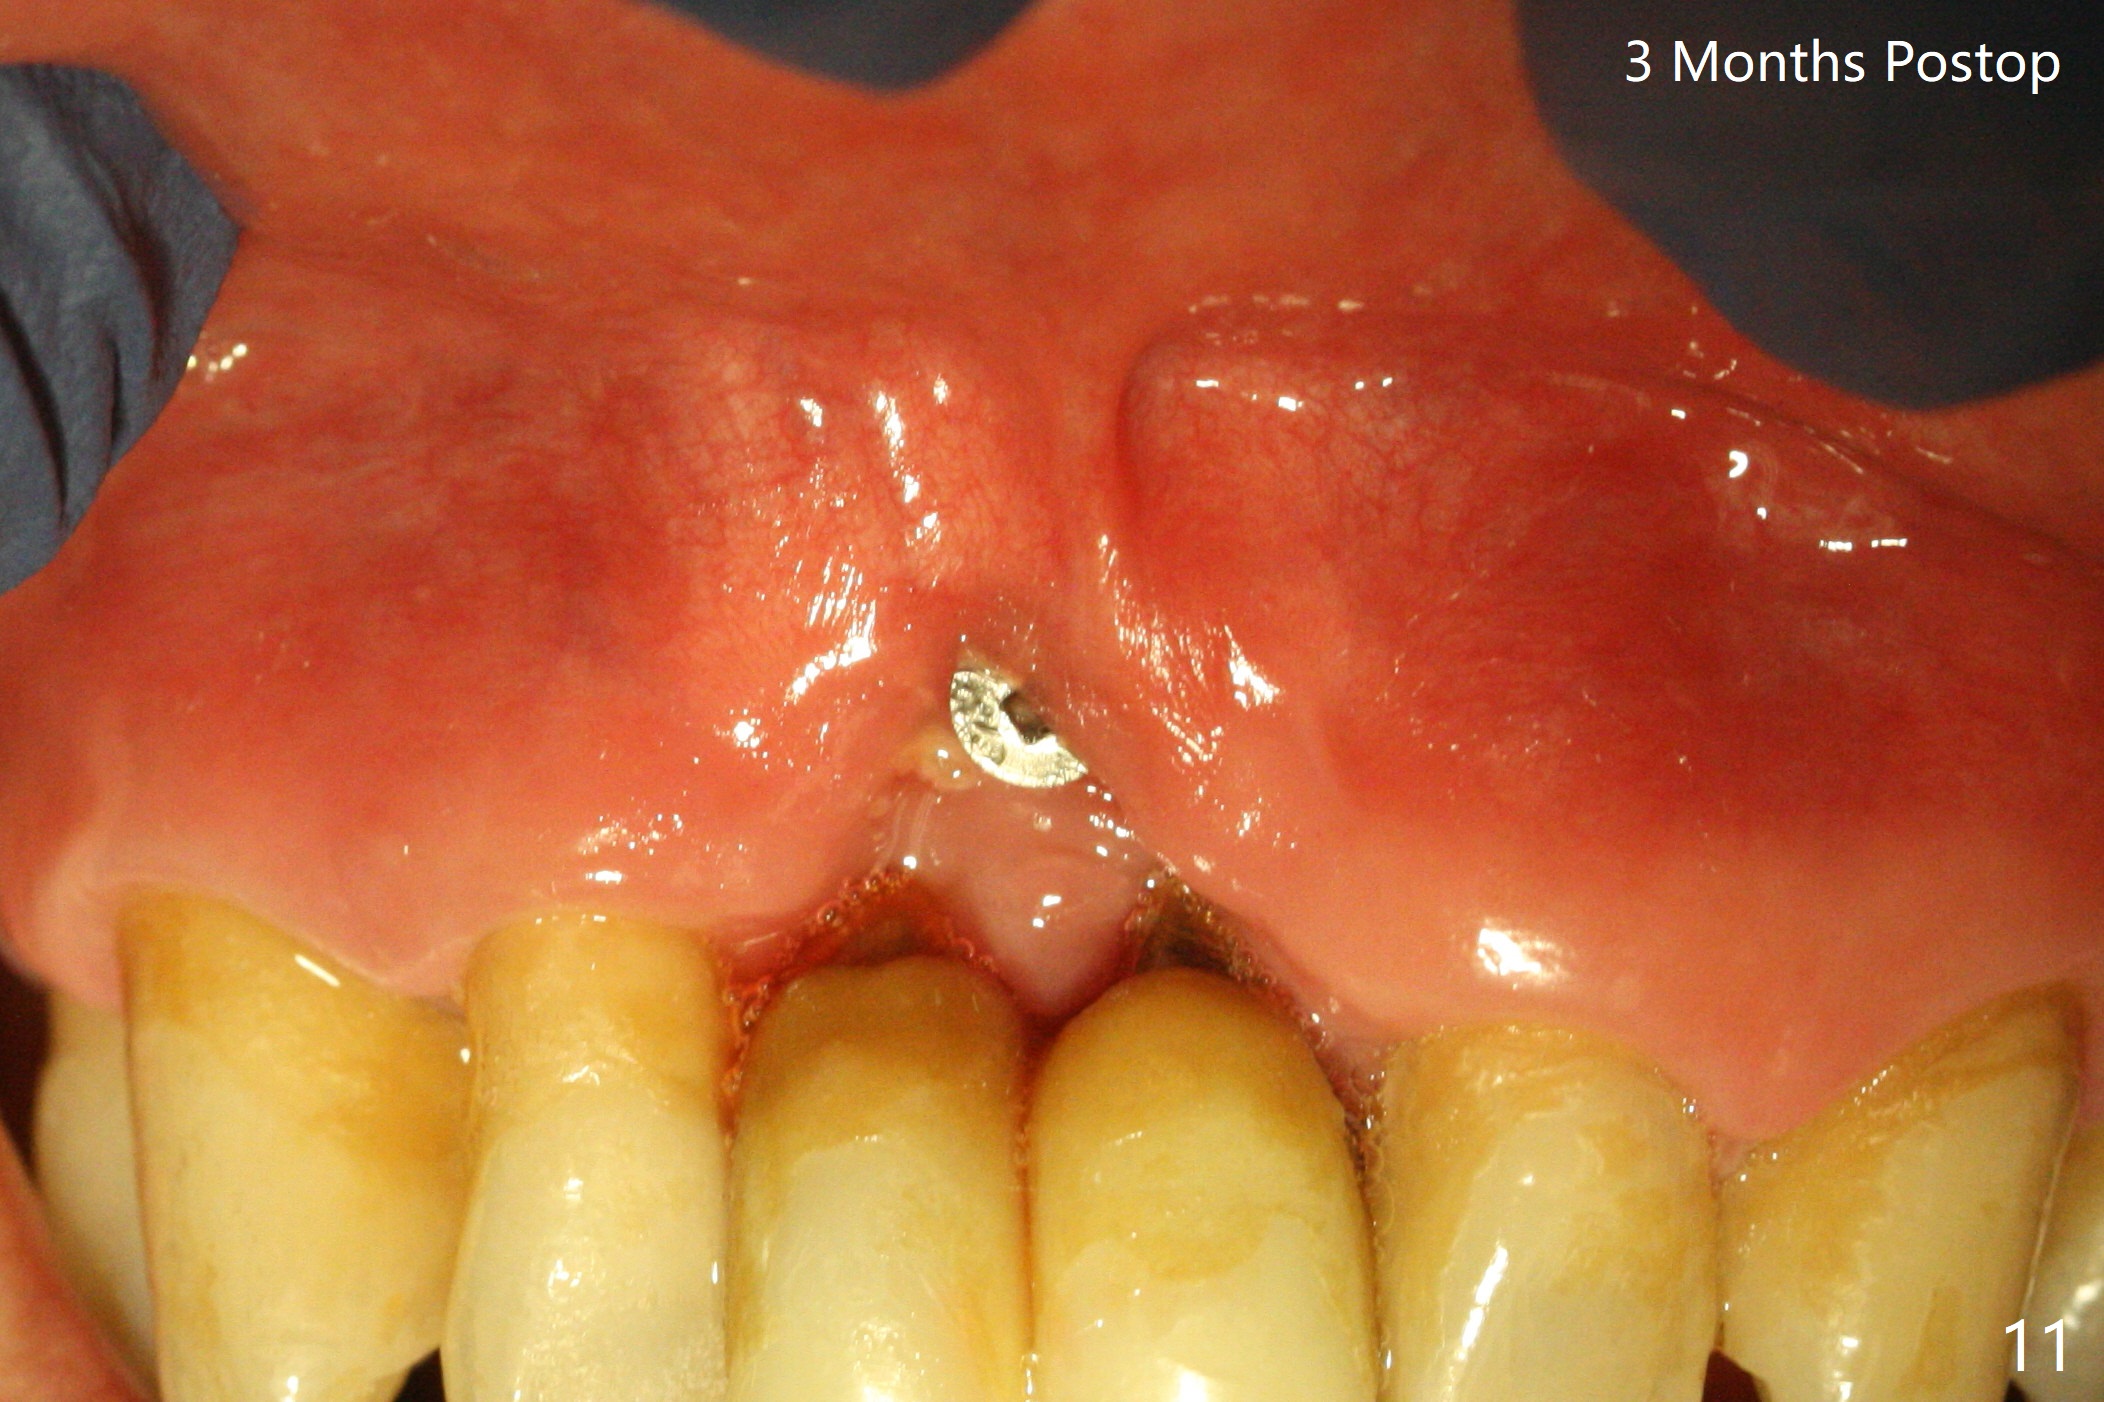

The gingiva remains recessive at #8 and 9 six months post immediate implant placement with bone graft (Fig.1). The buccal plate at #8 is particularly concave before (Fig.2 *) and after (Fig.3) abutment removal. The bony defect repair is assisted by placing a 4 mm tenting screw between the 2 implants (Fig.4) and placing allograft mixed with PRF (as putty) around the screw (Fig.5 (after replacement of the abutments)). The buccal contour improves because of the tenting screw and the bone graft placement (Fig.6 (as well as PRF and 6-month membranes)). The wound dehisces 12 days postop and immediately before leaving country for months (Fig.7). The sutures are removed, Osteogen plug is inserted (Fig.8) and periodontal dressing is applied (Fig.9). PA is taken to show the tenting screw (Fig.10 T). The latter is exposed 3 months postop (Fig.11,12). It appears that gingival graft is a must (Fig.13). Make a palatal stent, remove the temp with abutments and create a bleeding surface before harvesting a large piece of tissue. Connective tissue graft is done 5 months post bone graft (Fig.14). In fact there is no implant thread exposure. In fact the connective tissue graft does not survive. The abutments are re-prepared for pink porcelain (Fig.15). The bone loss is stable 1 year post cementation in spite of incomplete abutment seating (Fig.16). The soft tissue is nearly normal (Fig.17).